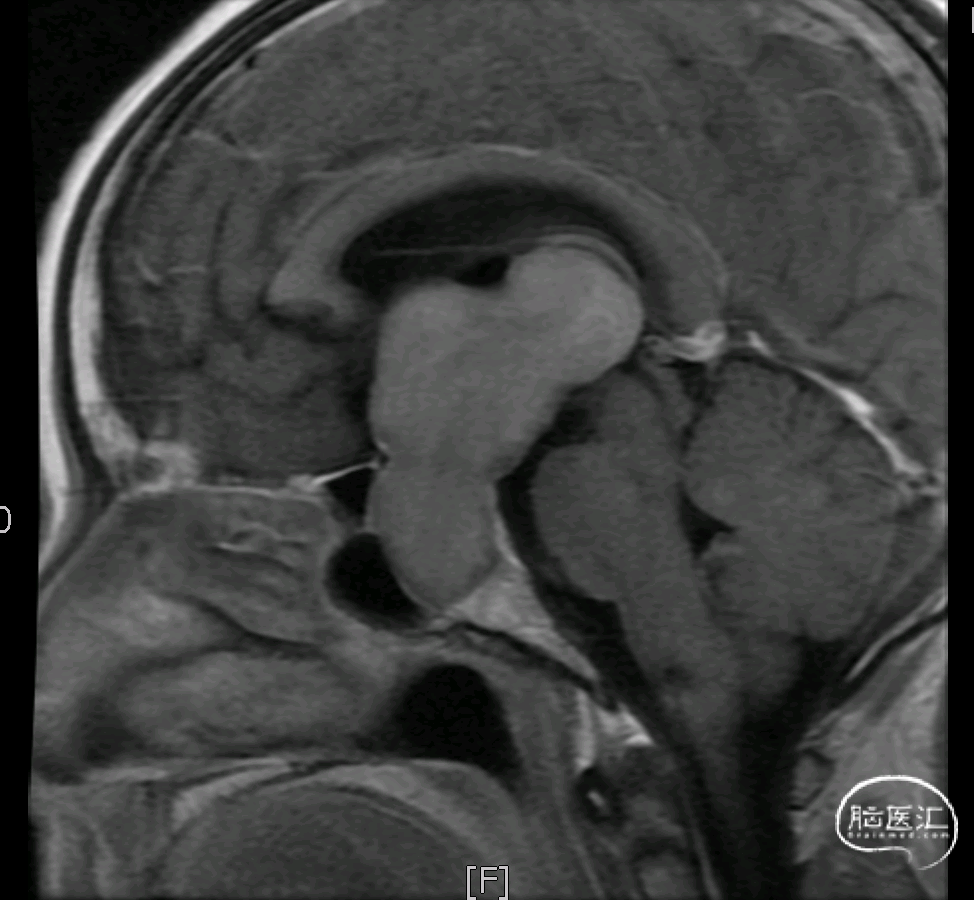

术前核磁示:巨大垂体腺瘤。

依据术前影像学病灶位置拟定神经内镜下扩大经蝶入路切除肿瘤

切除突入鞍上及第三脑室的肿瘤,可见三脑室内结构

巨大复杂型垂体腺瘤是突破鞍隔往颅内生长的肿瘤,近年来随着高清内镜的引入、颅底修补的完善和脑外科手术理念的进步,巨大复杂型垂体腺瘤可以通过扩大经鼻入路(EEA)手术得到很好的切除。采用扩大经鼻入路,利用内镜的宽广视野,增加了额外的工作空间,可以充分显露并安全的切除向鞍上生长的肿瘤,将一个深部病变转变为一个浅部病变来处理,具有更好的可操作性和更高的肿瘤切除率,这也是内镜经鼻鞍上入路处理复杂鞍区肿瘤的最大优势所在。